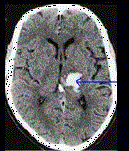

问题 患者,59岁,有高血压病史5年,因突发头痛,右侧肢体无力1天入院,行头颅如图所示部位出血,可诊断为 ( )

选项 A、左丘脑出血 B、右丘脑出血 C、左颞叶出血 D、左尾状核 E、左壳核出血

答案 A